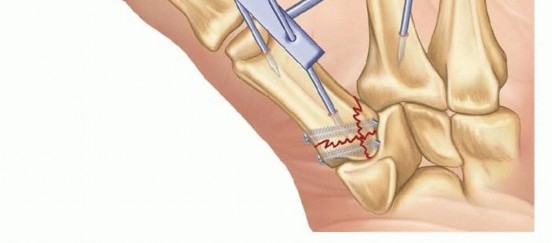

Open Reduction and Internal Fixation (ORIF) - Wagner Approach

For fractures with large volar-ulnar fragments (>20% of the articular surface), displaced Rolando fractures, or cases where closed reduction fails, ORIF is unequivocally mandated. The classic Wagner approach provides unparalleled exposure to the thumb CMC joint. A curvilinear incision is made along the glabrous border of the thenar eminence, curving dorsally at the level of the CMC joint.

Image

Meticulous superficial dissection is required to identify and protect the sensory branches of the superficial radial nerve dorsally and the palmar cutaneous branch of the median nerve volarly. The thenar musculature (abductor pollicis brevis and opponens pollicis) is sharply elevated from the metacarpal shaft and retracted volarly. The joint capsule is then incised longitudinally or in an L-shaped fashion to expose the articular surface. The hematoma is evacuated, and the fracture fragments are meticulously debrided of interposed soft tissue.

For a large fragment Bennett fracture, the shaft is reduced to the volar-ulnar fragment using a pointed reduction clamp. Provisional fixation is achieved with a K-wire. A 1.5mm or 2.0mm lag screw is then placed perpendicular to the fracture plane. The near cortex must be overdrilled (gliding hole) and the far cortex underdrilled (thread hole) to achieve true interfragmentary compression. The screw head should be countersunk to prevent hardware prominence beneath the thenar muscles.